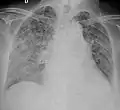

X-ray, 22 days after onset, showing extensive bilateral reticulo-nodular infiltrates